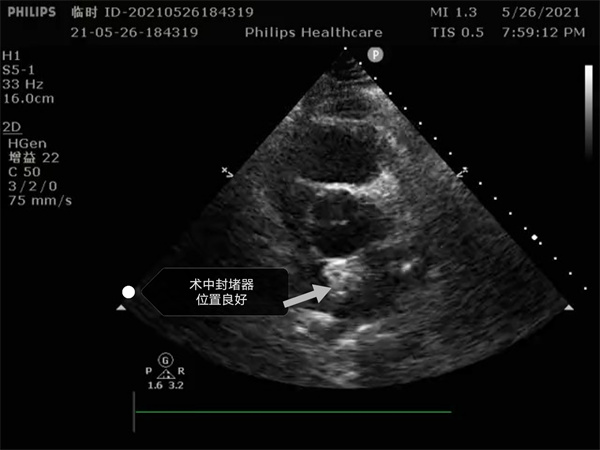

尤其是患者是個三房心,正常的人是有二個心房,這是一種少見的先天性心臟畸形, 如何在三房心把這個洞堵住,而且不影響心臟正常結構,是這個手術難點。沈主任組織全科進行術前討論,5月26日下午5點開始手術,導絲如何在不規(guī)則的只有米粒大小的卵圓孔里通過,鞘管如何通過,如何進入卵圓孔連接的副房,避免封堵器夾住隔膜,這些難點在術中被沈主任團隊一一化解,手術歷時二小時,隨著封堵器成功釋放,導管室外響起來熱烈的掌聲。

就這樣三房心合并卵圓孔未閉發(fā)生過三次腦梗的患者,在安康市中心醫(yī)院心內科導管室成功進行了國內第二例介入封堵手術。